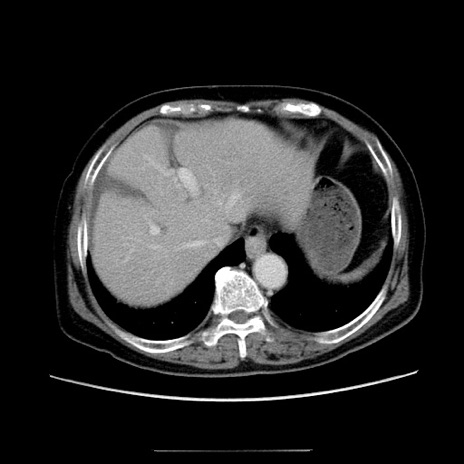

冠状断像

【症例】70歳代女性

【主訴】お腹が張る

【現病歴】1週間くらい前から腹部膨満の自覚あり。昨日夜から増悪したため、本日救急外来受診。

【身体所見】意識清明、BT 36.5℃、BP 165/106mmHg、HR 80bpm、SpO2 98%、腹部:膨満、軟、自発痛・圧痛なし、触診にて不快感あり、腸蠕動音:減弱

【データ】WBC 12600、CRP 1.04